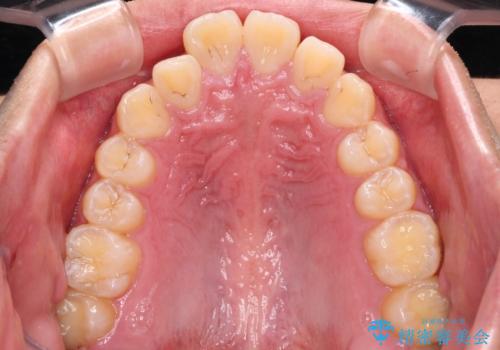

- 深く咬みこんだ前歯と、それに伴い前方に突出した上顎前歯を気にして来院された患者様です。

下顎の歯列は、奥歯が前方に傾斜し、前歯が上顎の歯の付け根に食い込むように内側に傾斜していました。

また、左右の犬歯の位置関係は上顎歯列が前方に位置する咬み合わせとなっており、インビザライン単体で治療するよりは、ワイヤー装置や補助装置を併用した方がより良い仕上がりになることが期待されました。

来院時は学生であったので、補助装置により上顎臼歯を後方に移動させ、下顎歯列はワイヤー装置による傾斜を改善させ、就職のタイミングでインビザラインにて仕上げていくこととしました。